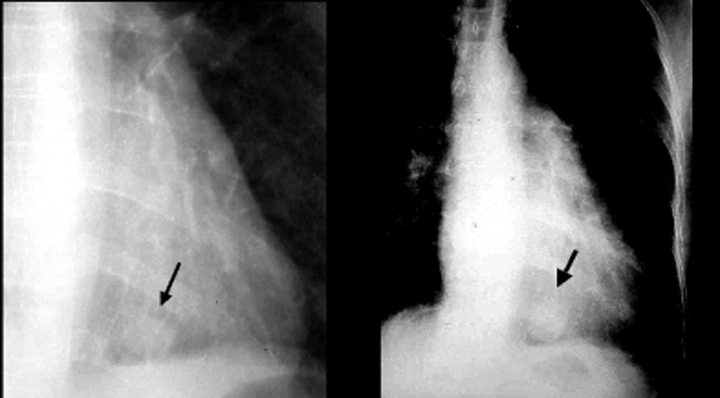

broncho Alveolar Cell Carcinoma - Solitary pulmonary nodule